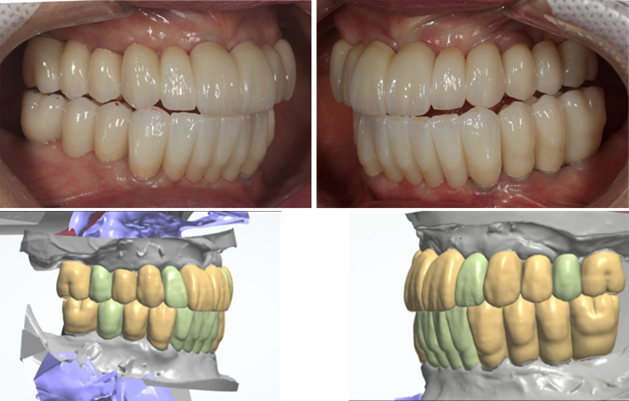

- Courtesy of Dr. Jong Cheol Kim, Korea

Dr. Jong Cheol Kim, edentulous, digital full-mouth prosthetics, digital guided surgery, guided surgery,R2 Studio, R2GATE Digital Oral Design, R2GATE DOD,flapless, AnyRidge, R2GATE, R2GATE full surgical Kit

AnyRidge implant system, R2GATE Guide, R2GATE surgical kit, R2GATE DOD, R2 Studio